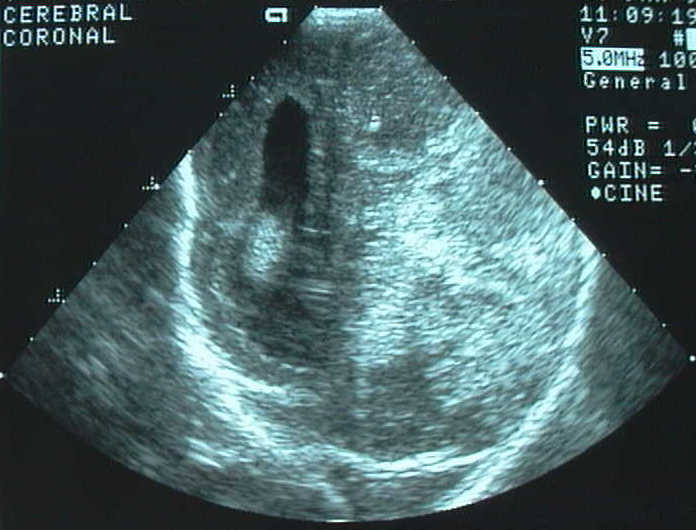

Se trata de un recién nacido que ingresa en la Unidad de cuidados intensivos neonatales de nuestro hospital por prematuridad y tumoración intracraneal; es fruto de una 3ª gestación, de 31 semanas de evolución y peso adecuado, con antecedentes de aborto anterior. Las ecografías practicadas a las 12 y 19 semanas son congruentes. A las 31 semanas se detecta ecográficamente una tumoración irregular de 57x44 mm en hemisferio cerebral izquierdo que desplaza la línea media, heterogénea, con dilatación de asta posterior del ventrículo contralateral. A continuación inicia dinámica uterina, practicándose cesárea por sufrimiento fetal. Al ingreso, se baraja el diagnóstico de teratoma cerebral frente al de hematoma asociado a presunta plaquetopenia. A la exploración, destacan hipoactividad y macrocefalia con diástasis de suturas.

Figura 1 : Imagen por ecografía (a) y por Tomografía Computada con contraste (b). Se observa una gran masa tumoral ocupando la mayor parte del hemisferio izquierdo e hidrocefalia derecha.